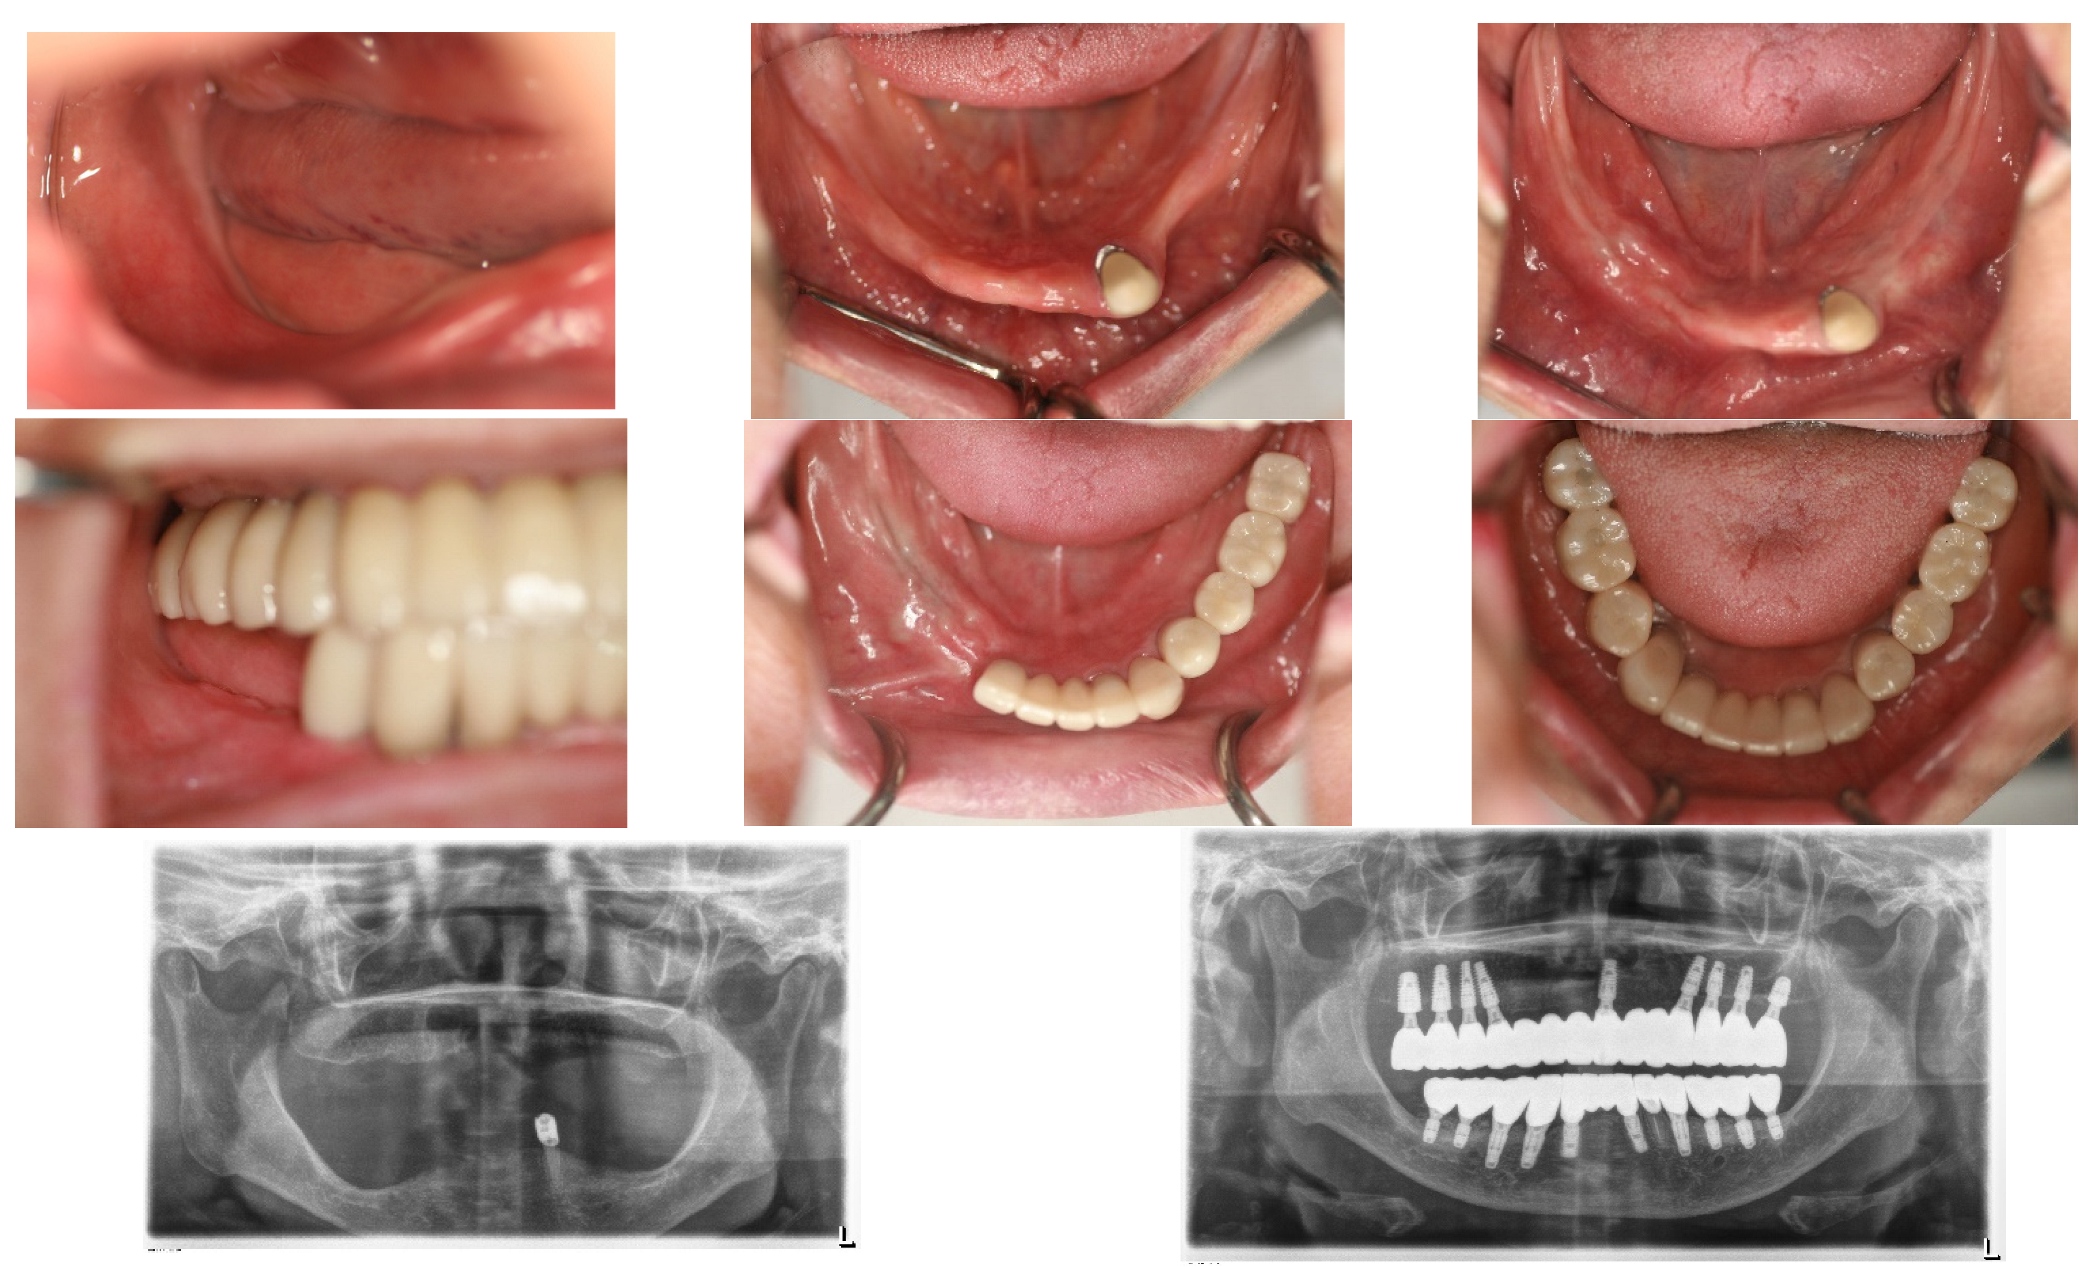

On 28 May 2015, a 1.3 mL SITE was inserted into the right edentulous ridge through a small pouch created by a 4 mm stab incision. On 2 June 2015, wound dehiscence occurred at the insertion site of the SITE on the right side, necessitating the removal of the SITE. Consequently, a new 0.7 mL SITE was inserted on 9 September 2015 (Figure 2).

Subsequently, on 1 June 2015, the same procedure was performed at the left posterior edentulous site of the mandible and a 1.3 mL SITE (Figure 3).

The SITEs were removed after achieving full expansion, in adherence to the manufacturer’s recommendations—82 days later on the left side (21 August 2015) and 37 days later on the right side (16 October 2015). The vertical bone augmentation procedures were conducted simultaneously. Xenograft material (Bio-Oss, produced by Geistlich, Wolhusen, Switzerland). Was utilized for the augmentation and covered with a Goretex titanium-reinforced membrane (produced by W. L. Gore & Associates in the Newark, Delaware, USA) through the same small openings used for the SITEs removal. The incisions were sutured with 4-0 Monocryl, and the stitches were removed two weeks later, revealing no significant wound dehiscence (Figure 4).

Following an 8-month period for bone consolidation, implants were then placed in the left lower posterior edentulous areas on 18 April 2016. A 4.5 × 9 mm OsseoSpeed TX implant from Astratec, Mölndal, Sweden, was used for the first premolar, and 4.3 × 7 mm and 4.8 × 8 mm Oneplant implants from Warrentec, Seoul, South Korea, were used for the second premolar and the first molar, respectively. Additionally, a 4.0 × 6.0 mm OsseoSpeed TX implant, also from Astratec, Germany, was placed (Figure 5).

Seven months following the first bone graft, performed on the day the SITE was removed from the right posterior area of the mandible, 5 × 9 mm OsseoSpeed TX implants (OsseoSpeed TX implant, Astra Tech, Mölndal, Sweden) were placed for the first premolar and the canine. However, the procedure to place implants in the molar area was deferred; instead, a second bone graft utilizing the GBR technique was conducted to augment the bone volume, ensuring it could accommodate implants of the appropriate size.

Figure 2. On 28 May 2015, a small incision was made in the right posterior edentulous site of the mandible, through which a Self-Inflating Tissue Expander (SITE) was inserted into a subperiosteal pouch and subsequently sutured. On 2 June 2015, wound dehiscence occurred at the insertion site of the SITE on the right side, necessitating the removal of the SITE. Consequently, a new 0.7 mL SITE was inserted on 9 September 2015.

Figure 3. On 1 June 2015, the same procedure was performed at the left posterior edentulous site of the mandible. Please note the use of a before-and-after template for predicting the final result.

Figure 4. Bone graft procedures were performed when the SITEs were removed after their full expansion. The GBR technique was used with xenograft (Bio-Oss large granule) and Gore-Tex TR membrane. The same small incisions used for removing SITEs on both sides were sufficient for GBR, thanks to the prior soft tissue expansion. The procedures were carried out on different dates for each side, with the left side being treated on 21 August 2015, and the right side on 16 October 2015.

Figure 5. After an 8-month waiting period for bone consolidation, implants were placed in the left posterior area following the removal of the Gore-Tex membrane. It is noteworthy to mention the well-matured bone achieved from the bone graft procedure. Photographs documenting this progression include one from the left side on 1 April 2016, the day the left natural canine crown was set; 18 April 2016, the day of the operation on the left posterior area of the mandible; and two images from the right side on 26 October 2016, the day of implant placements for the right second premolar and the right first molar, 6 months after the second bone graft.